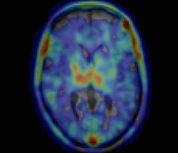

Positron Emission Tomography (PET)

The Siemens Biograph 6 PET/CT scanner features 6 slice CT, a multi-detector ring system and 3D reconstruction. An Allogg Automated Blood Sampling System (ABSS) is available for those studies which require arterial blood sampling; there is also an adjacent tissue/blood processing lab with dual-HPLC/radioactivity detectors for tracer metabolite analysis.